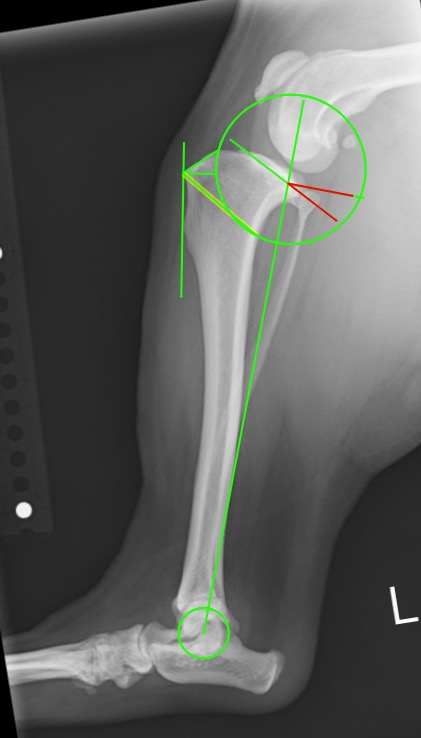

手術計画のための計測

TPLO法は膝の中にある傾斜を水平にして大腿骨と脛骨が滑ってずれる力を抑制し、結果的にうまく体重をかけられるようになる方法です。